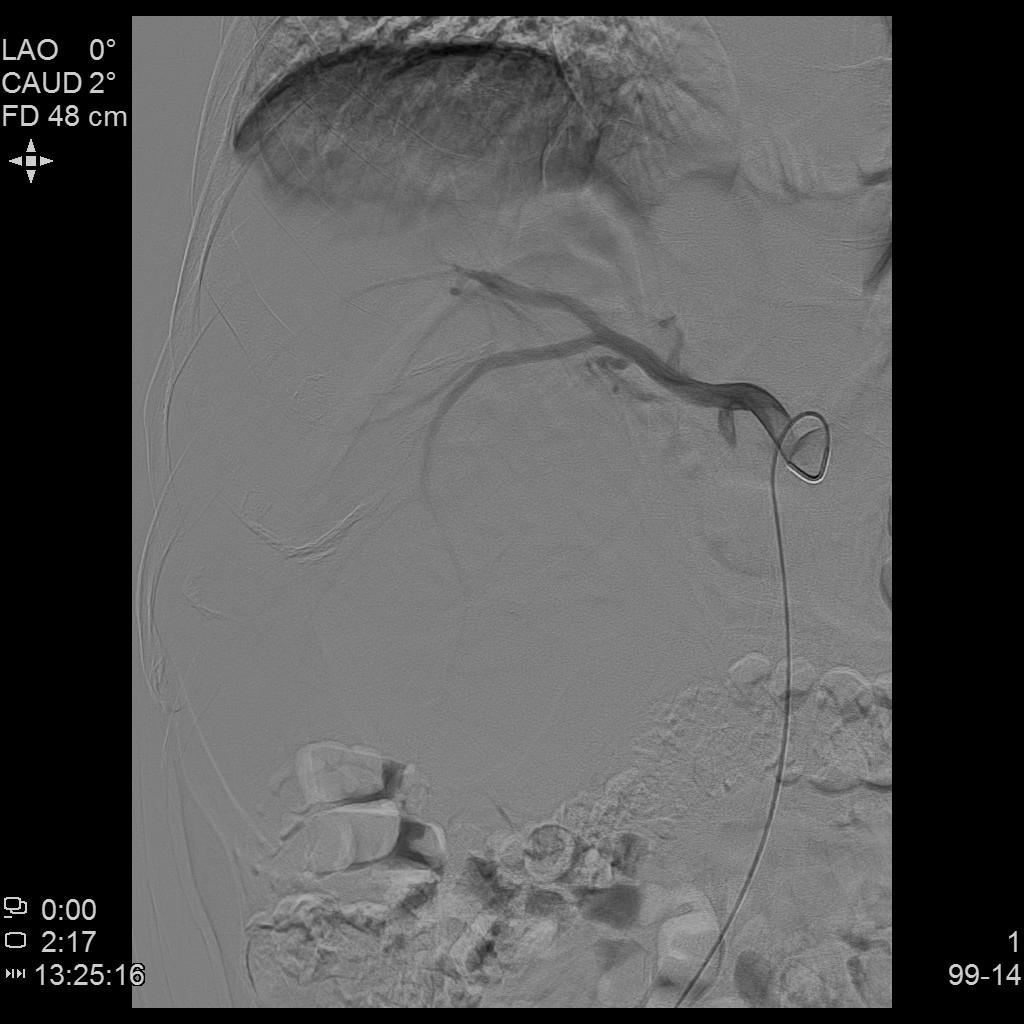

- TACE:考虑肝脏病灶巨大,分次栓塞治疗以提高患者耐受性及安全性。采用碘油栓塞联合载药微球栓塞肝内病灶。原发性肝癌介入栓塞利器——载药微球栓塞治疗(D-TACE)

DSA1